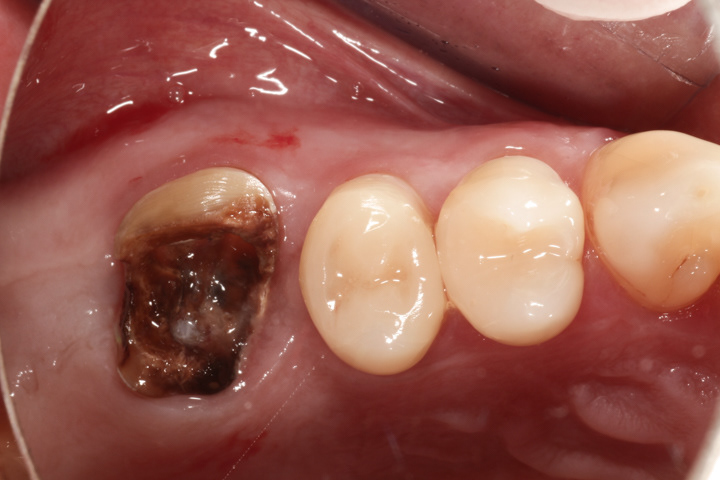

Poniżej przykład implantacji natychmiastowej tzn. takiej gdzie implant zostaje wszczepiony zaraz po ekstrakcji uszkodzonego zęba. Zaletą tej metody jest fakt, że zamiast dwóch zabiegów chirurgicznych, jest jeden.

PRZYPADEK 12